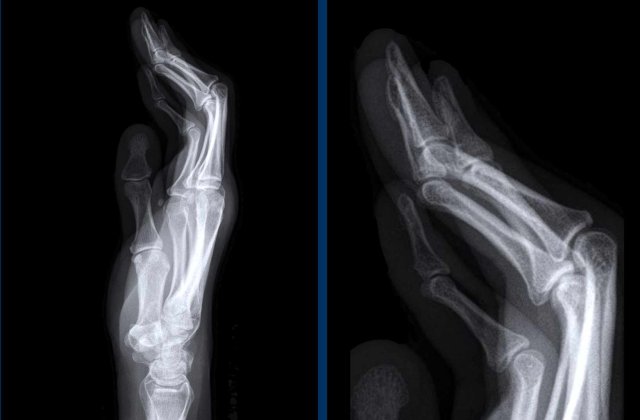

Sausage digits and pencil in cup deformity in Psoriatic arthritis Sausage digits and pencil in cup deformity in Psoriatic arthritis

Sausage digits

Typical appearance of dactylitis “sausage digits” with soft tissue swelling and pencil-in-cup deformity of DIP 1-2 and 5 of the left hand in a patient with psoriatc arthritis.

Notice that the MCP joints are not involved (unlike in RA).

Psoriatic arthritis Psoriatic arthritis

Progressive psoriatic arthritis

1. The picture on the left shows marginal erosions (black arrow) and subtle bone formation (blue arrow) of the IP joint.

2. Later on, it progresses to the typical pencil-in-cup deformation.

The distribution and the bone formation makes the diagnosis of rheumatoid arthritis unlikely.

The marginal erosions and the absence of DIP involvement in other joints makes the diagnosis of erosive osteoarthritis unlikely, although pencil-in-cup can look like the gullwing deformity in erosive osteoarthritis.